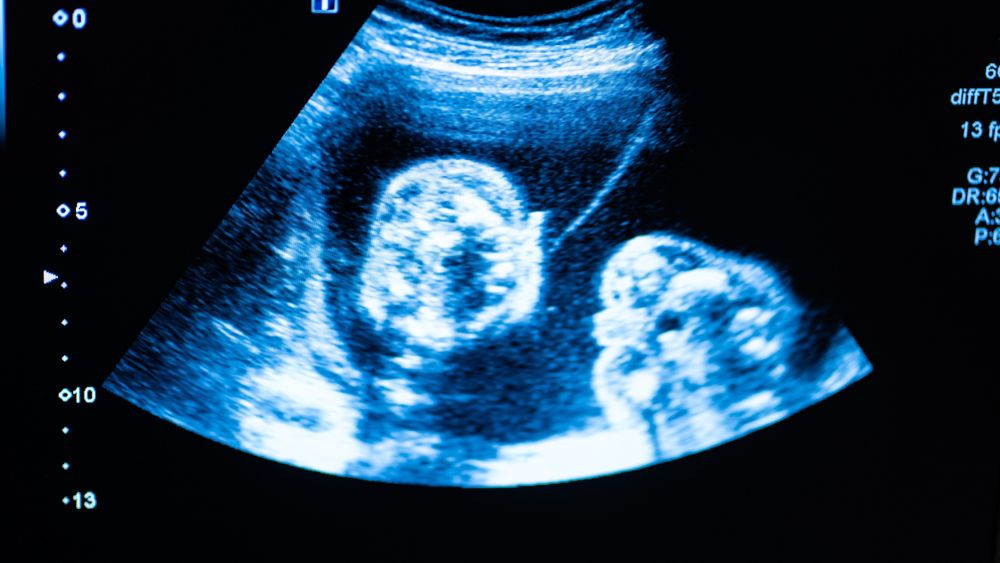

An anomaly scan is an important ultrasound done between the 18th and 22nd week of pregnancy to check your baby’s growth and development. Sometimes, your baby may stay in a position where the doctor cannot clearly see all organs. This can make the scan difficult and may require repeating it.

An anomaly scan (also called a fetal anatomy scan) helps doctors:

- Check the baby’s heart, brain, spine, and organs

- Detect structural abnormalities

- Monitor the baby’s overall growth. It is usually performed in the second trimester (18–22 weeks).